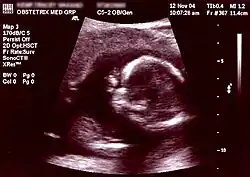

![]() Obstetric sonogram of a fetus at 16 weeks. The bright white circle center-right is the head, which faces to the left. Features include the forehead at 10 o'clock, the left ear toward the center at 7 o'clock and the right hand covering the eyes at 9:00. | |

Obstetric ultrasonography, or prenatal ultrasound, is the use of medical ultrasonography in pregnancy, in which sound waves are used to create real-time visual images of the developing embryo or fetus in the uterus (womb). The procedure is a standard part of prenatal care in many countries, as it can provide a variety of information about the health of the mother, the timing and progress of the pregnancy, and the health and development of the embryo or fetus.

The International Society of Ultrasound in Obstetrics and Gynecology (ISUOG) recommends that pregnant women have routine obstetric ultrasounds between 18 weeks' and 22 weeks' gestational age (the anatomy scan) in order to confirm pregnancy dating, to measure the fetus so that growth abnormalities can be recognized quickly later in pregnancy, and to assess for congenital malformations and multiple pregnancies (twins, etc).[1] Additionally, the ISUOG recommends that pregnant patients who desire genetic testing have obstetric ultrasounds between 11 weeks' and 13 weeks 6 days' gestational age in countries with resources to perform them (the nuchal scan). Performing an ultrasound at this early stage of pregnancy can more accurately confirm the timing of the pregnancy, and can also assess for multiple fetuses and major congenital abnormalities at an earlier stage.[2] Research shows that routine obstetric ultrasound before 24 weeks' gestational age can significantly reduce the risk of failing to recognize multiple gestations and can improve pregnancy dating to reduce the risk of labor induction for post-dates pregnancy. There is no difference, however, in perinatal death or poor outcomes for infants.[3]